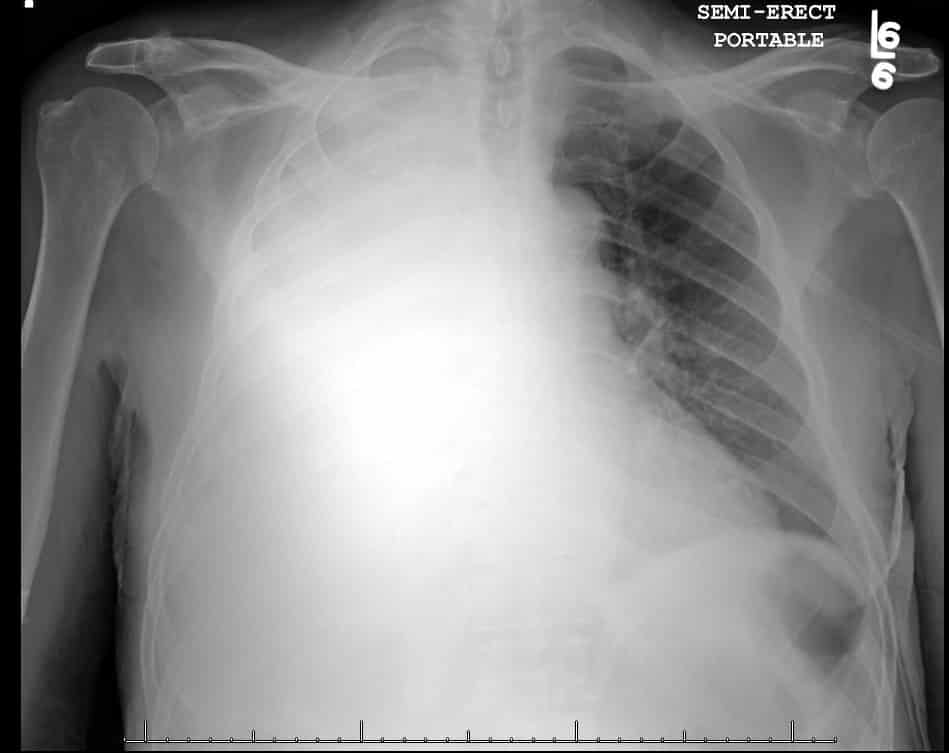

Bản chụp X-quang hai lá phổi của một bệnh nhân bị đông đặc. Phần bị hư hại màu trắng mờ, phần màu đen còn có thể hoạt động. (Ảnh minh họa: Emory Medical School).

Sức khoẻ bệnh nhân 91 ngày 13/5 tiếp tục tiên lượng rất xấu. Cả 2 lá phổi của bệnh nhân bị xơ hóa đông đặc, chỉ còn khoảng 10% có thể hoạt động. Nếu không có máy ECMO hỗ trợ, bệnh nhân sẽ tử vong. Hiện, cách duy nhất để cứu bệnh nhân là ghép phổi.